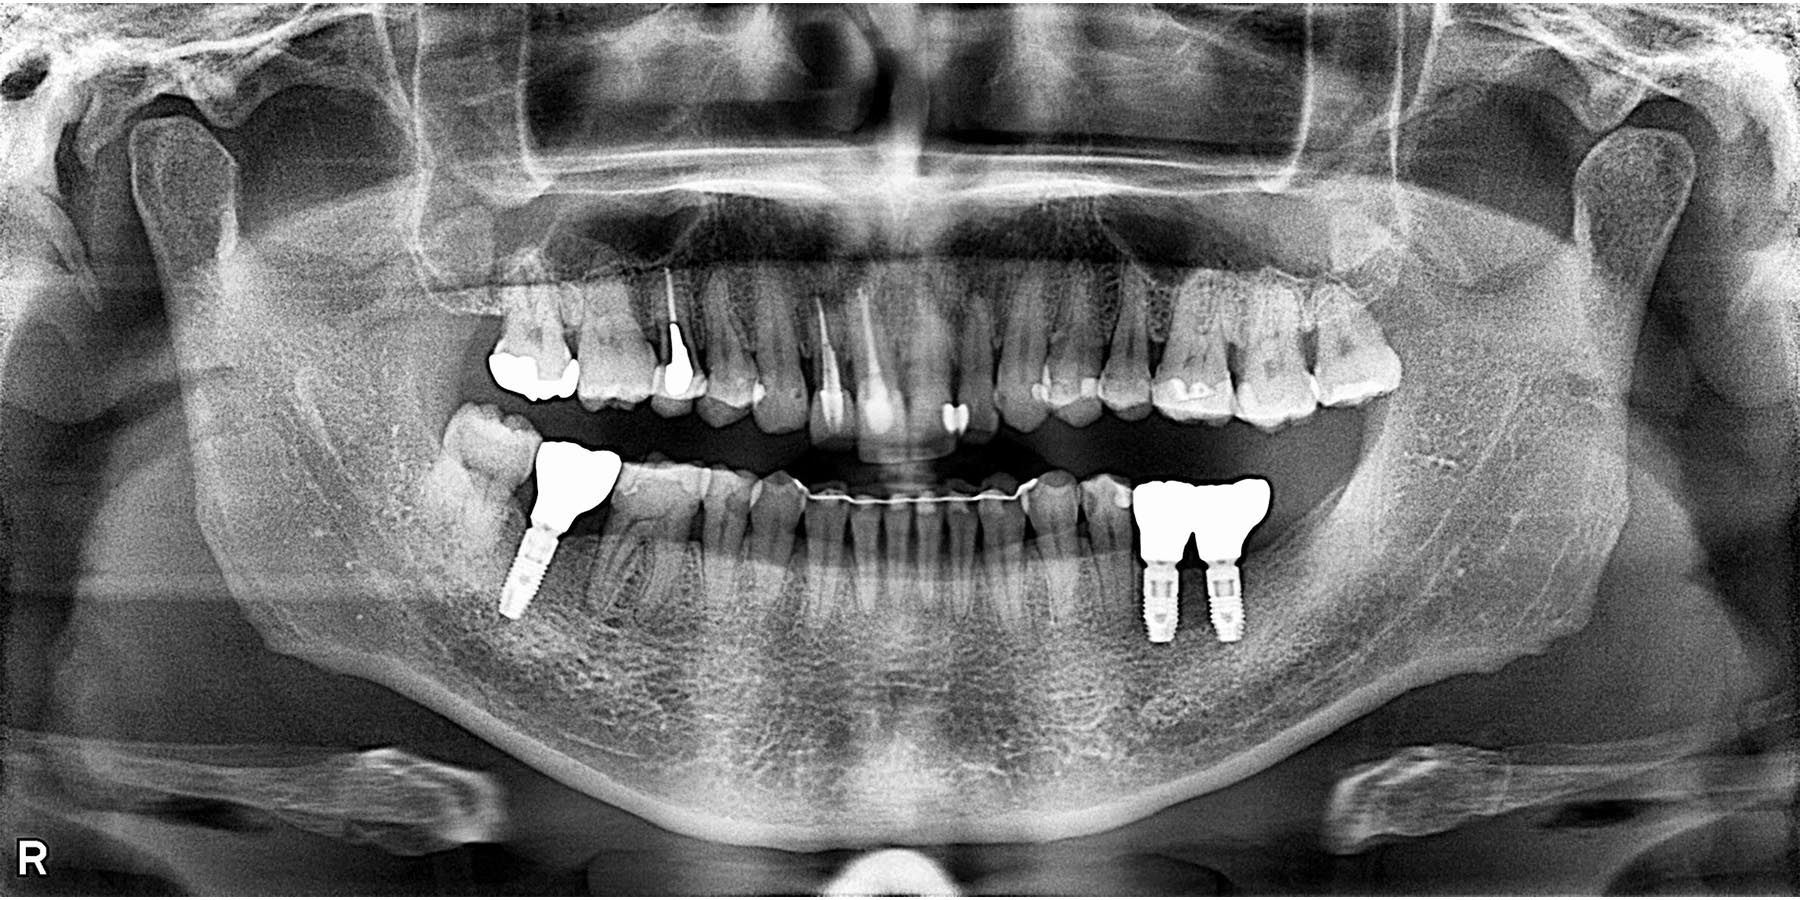

治療後

| 治療内容 | 矯正治療(前歯部) 右下7.左下5.6インプラント治療(3本) 前歯、奥歯セラミック治療(5本) |